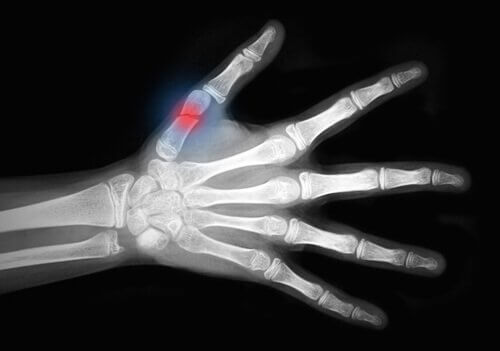

Denne sygdom svækker dine knogler, hvilket gør dem skrøbelige og sårbare overfor brud. Dit håndled, hofter eller rygsøjle er de områder, der har størst risiko for brud.